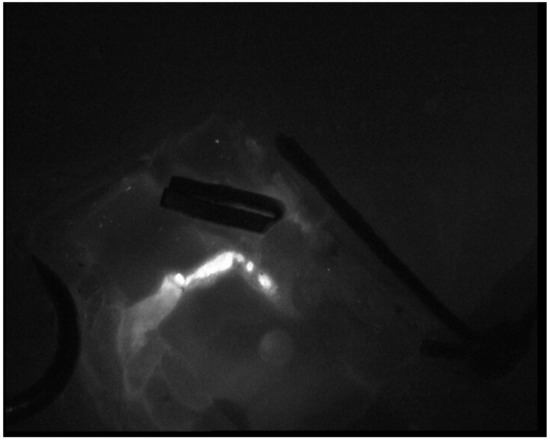

Surgical Technique